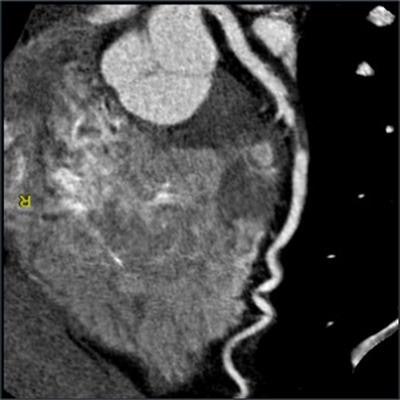

In addition to CCTA being the only noninvasive imaging modality that provides a reliable depiction of the coronary arteries, numerous large-scale trials have demonstrated the test's capacity to improve the diagnosis of obstructive CAD as well, Maroules and colleagues noted.

What's more, combining noninvasive functional tests such as CT myocardial perfusion and CT fractional flow reserve with CCTA provides clinicians with more information concerning coronary stenosis. Ultimately, these benefits may enable CCTA to detect pathology and prevent unnecessary invasive procedures more efficiently than other methods.